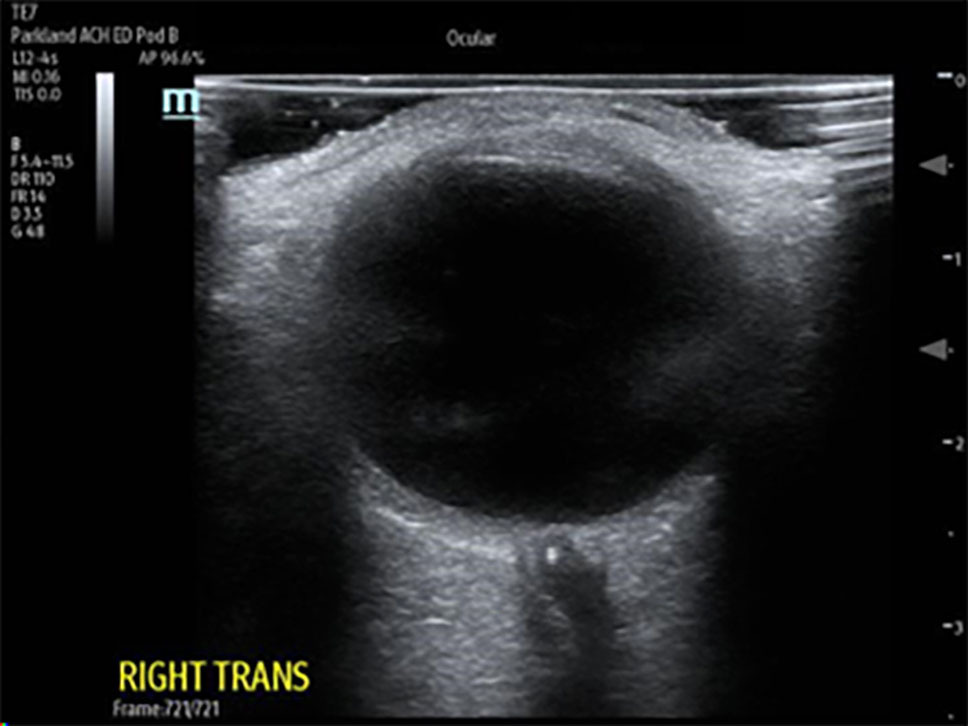

In CRAO, a dense retrobulbar spot sign (RBSS) can be seen immediately posterior to the globe as a hyperdense embolism visualized in the central retinal artery. It is the equivalent of the dense middle cerebral artery sign seen in strokes, and in studies has a sensitivity of 83% and a specificity of 100%.35,36 (See Figure 4.)

Figure 4. Retrobulbar Spot Sign Consistent with Central Retinal Artery Occlusion |

![]() |

Ocular point-of-care ultrasound (POCUS) showing dense retrobulbar spot sign, consistent with central retinal artery occlusion (CRAO) Courtesy of Dustin Williams, MD |